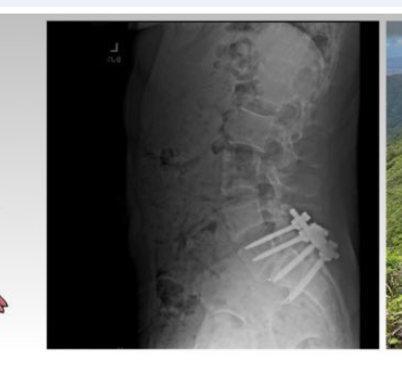

He has this X-ray as part of his banner on his twitter profile

image.png